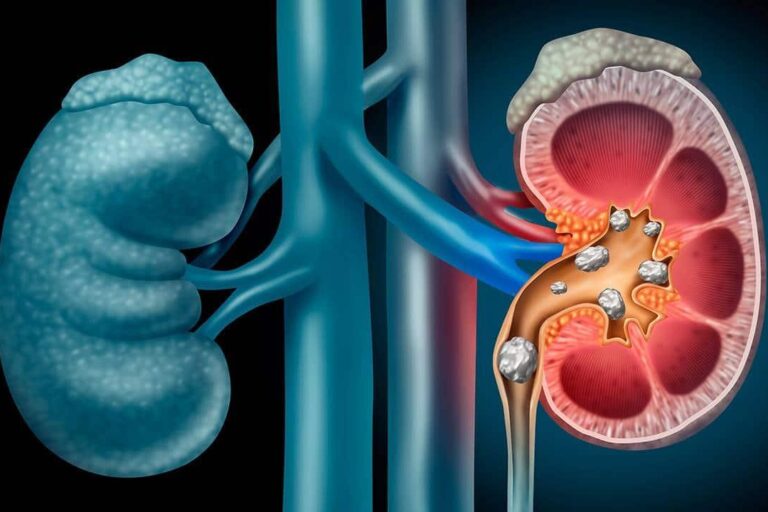

Litiasis urinaria. Estudio metabólico en pacientes afectados. Congreso Nacional de Urología LXXXVIII Reunión Nacional de los Grupos de Litiasis, Endourología,…